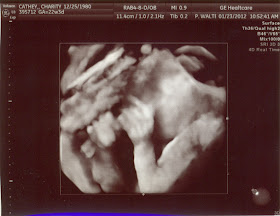

Ultrasound pictures

Here are the ultrasound pictures of our new bundle of joy.

Here's a profile picture.

It's a boy!

Here are his feet.

And tiny little toes.

Then the technician switched to 3D as she tried out her new machine.  Here's his little face.

And arms and hands.

And his little legs.  We love him already.